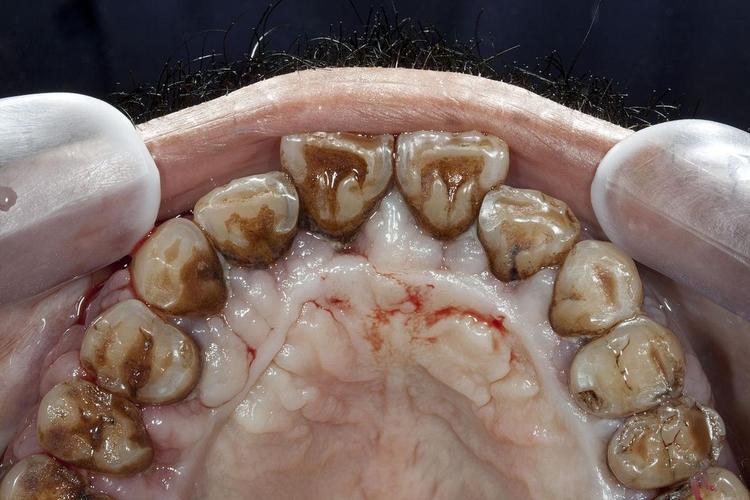

- 牙周炎会导致牙槽骨持续吸收、破坏,骨质变得疏松、薄弱,在这种不健康的、发炎的骨组织上种植,骨结合的质量和成功率会大大降低,种植体可能无法稳固地扎根,甚至松动、脱落。

- 牙周炎意味着口腔内存在大量的致病细菌,尤其是在牙周袋深处。

- 种植手术是一个有创操作,如果牙周炎未得到控制,这些细菌很容易在手术过程中或术后进入种植区域,引起种植体周围炎(一种更难治疗、破坏性更强的炎症,会导致种植体周围骨吸收,最终导致种植失败)或手术创口感染。

- 洁治(洗牙): 清除牙齿表面和牙龈上方的牙菌斑和牙结石。

- 龈下刮治和根面平整: 这是关键步骤,深入到牙龈下方,清除牙周袋内(牙龈与牙根之间)的牙菌斑、牙结石,并刮除受牙结石污染、变得粗糙的牙根表面,使牙龈重新附着,这通常需要分象限进行,可能需要多次复诊。